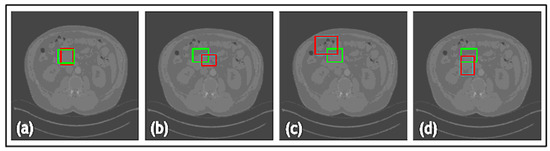

- In TED, the transformer is adapted to take in images and slide across Regions of Interest (ROIs) provided by AGs. This design aims to adaptively deal with different types of noise artifacts and thus effectively detect a variety of anomalies including tooth decay and numerous lesions across two modalities.

- A new loss function is proposed along with TED, which combines a sliding box, Intersection Over Union (IOU), and Mean Squared Error (MSE). It compares the IOU and MSE between the predicted and real bounding boxes to evaluate the regions of focus chosen by the AGs.